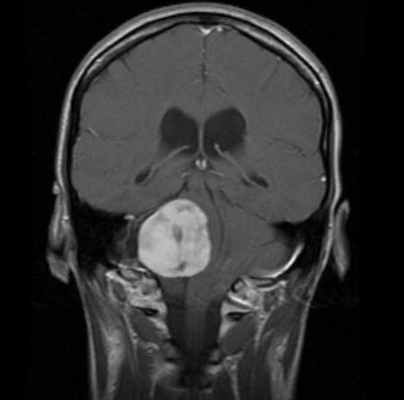

Сканирование головы: если другие тесты показывают, что у пациента может быть вестибулярная шваннома, для подтверждения диагноза используется магнитно-резонансная томография (МРТ). МРТ использует магнитные поля и радиоволны, а не рентгеновские лучи для создания подробных изображений мозга. Томография показывает «срезы» мозга, которые можно объединить для создания трехмерного изображения опухоли. Часто пациенту вводят контрастный краситель. Опухоль впитывает больше красителя, чем нормальная ткань мозга, и будет четко видна на сканировании. МРТ обычно показывает опухоль во внутреннем слуховом проходе.

Оптимальными способами визуальной диагностики являются компьютерная томография (КТ) и магнитно-резонансная томография (МРТ) головного мозга. Эти исследования принято проводить с контрастным усилением, так как оно позволяет обнаружить даже небольшие новообразования [14] . Иногда опухоль обнаруживается случайно — при проведении КТ или МРТ головного мозга по другому поводу [13] . По результатам этих исследований можно поставить точный диагноз, выявить локализацию опухоли, её размеры, структуру, отношение к окружающим тканям задней черепной ямки, спланировать тактику хирургического или радиологического лечения [12] .